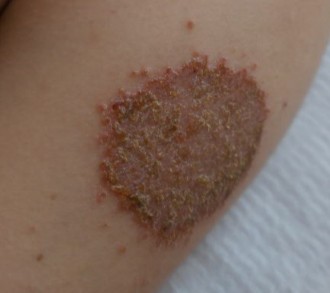

1생기 치료 사례는 생기한의원 각 지점별 실제 치료 환자의 동의를 받아 공개하는 내용입니다.

2생기 치료 사례는 동일인의 치료 전후 사진을 인위적 수정하지 않은 내용입니다.

3각 환자의 상태와 특성에 따라 치료 효과에 차이가 있을 수 있고, 일반적 부작용이 나타날 수 있습니다.

4치료 부위의 특성상 공유하지 못한 다양한 생기 치료 사례는 각 지점에서 안내 도와드리겠습니다.

치료사례